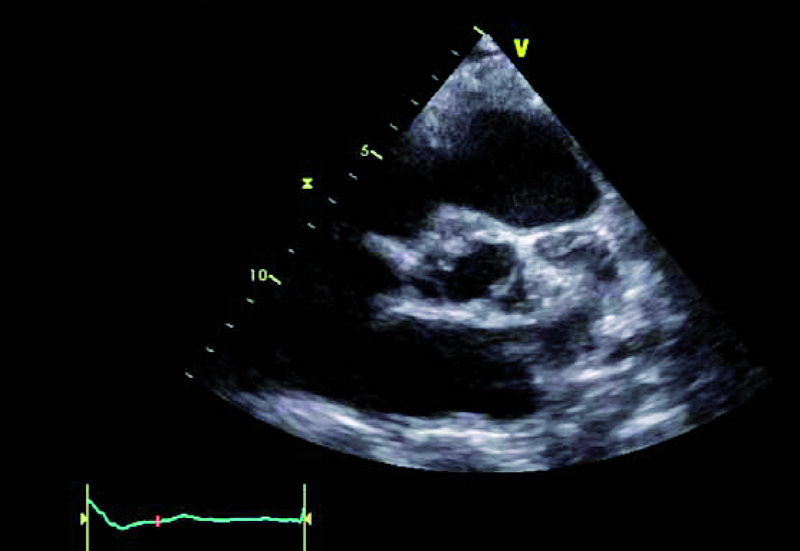

Kobieta, lat 41. Jakie patologie można rozpoznać na zamieszczonych rycinach?

2. Dwupłatkowa zastawka aortalna (ryc. 2).